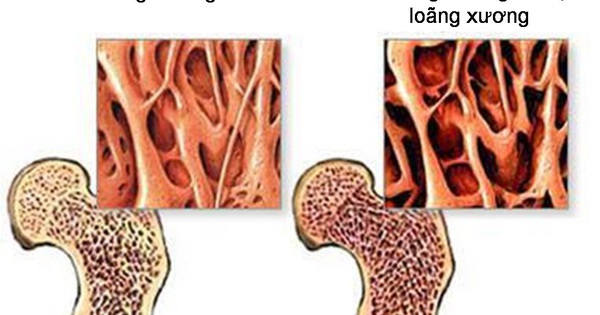

Cùng với quá trình lão hóa, hệ xương của con người trải qua sự suy giảm tự nhiên về mật độ khoáng, cấu trúc và độ bền. Đây là yếu tố nền dẫn đến loãng xương – tình trạng xương trở nên giòn, dễ gãy, đặc biệt ở các vị trí như cột sống, cổ xương đùi và cổ tay. Để duy trì xương chắc khỏe, việc chăm sóc dinh dưỡng và tập luyện là vô cùng quan trọng.

Theo các tổ chức y tế quốc tế, nguy cơ loãng xương tăng rõ rệt sau tuổi 50, nhất là ở phụ nữ sau mãn kinh do giảm estrogen. Không chỉ yếu tố tuổi tác, nhiều thói quen sống hằng ngày cũng tác động trực tiếp đến sức khỏe xương.

Nguy cơ loãng xương tăng rõ rệt sau tuổi 50, nhất là ở phụ nữ sau mãn kinh do giảm estrogen.

Sức khỏe xương không chỉ liên quan đến nguy cơ gãy xương mà còn ảnh hưởng trực tiếp đến khả năng vận động và mức độ độc lập của người cao tuổi. Khi xảy ra gãy xương, đặc biệt là gãy xương hông, người bệnh có thể phải đối mặt với thời gian hồi phục kéo dài, thậm chí mất khả năng tự chăm sóc. Vì vậy, việc ưu tiên bảo vệ xương ngay từ sau tuổi 50 là cần thiết.